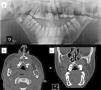

Mandibular or odontogenic keratocysts (Fig. 4). Such lesions are found in between 74% and 90% of patients with Gorlin syndrome.11,27 Onset may occur at ages between 4 and 5 years and they appear before 20 years in 75% cases27 but rarely develop in patients aged over 30 years. They are asymptomatic and are located on both sides of the jaw, and usually multiple lesions are present.10 Occasionally they undergo malignant transformation to ameloblastomas11 and squamous cell carcinoma.21

Figure 4.Odontogenic keratocysts in a patient with Gorlin syndrome. A, Panorex of the jaw, where keratocysts can be seen enveloping several molars. B, Axial computed tomography section in which maxillary odontogenic keratocysts can be seen. C, Coronal computed tomography section, showing maxillary keratocysts compressing the paranasal sinuses. Courtesy of Dr. E. García Esparza.